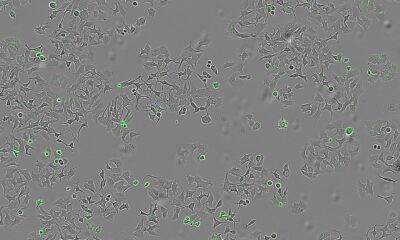

Български учен разработи иновативен медикамент, който спира растежа на ракови тумори и предотвратява метастазите. Асистент проф. д-р Здравка Медарова, водеща фигура в съвременната РНК-медицина, е начело...